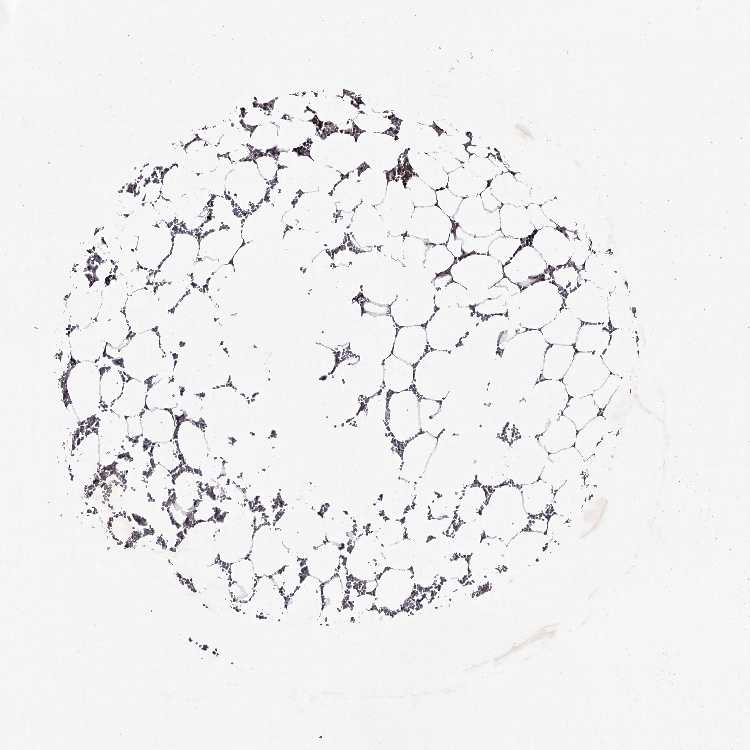

BONE MARROW - Antibody stainingi

Antibody staining in the annotated cell types in the current human tissue is reported as not detected, low, medium, or high, based on conventional immunohistochemistry profiling in selected tissues. This score is based on the combination of the staining intensity and fraction of stained cells.

Each image is clickable and will lead to virtual microscopy that enables deeper exploration of all samples and also displays staining intensity scores, fraction scores and subcellular localization as well as patient and tissue information for each sample.

Antibody HPA038981

Hematopoietic cells Low